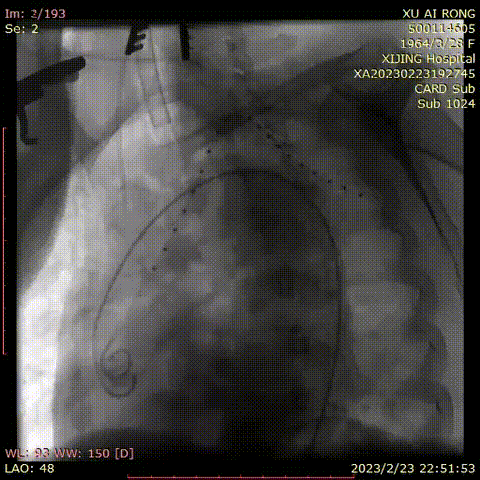

术前造影

导入弓部

主体支架

释放弓部

超选左颈总动脉

超选无名动脉

并预置导丝